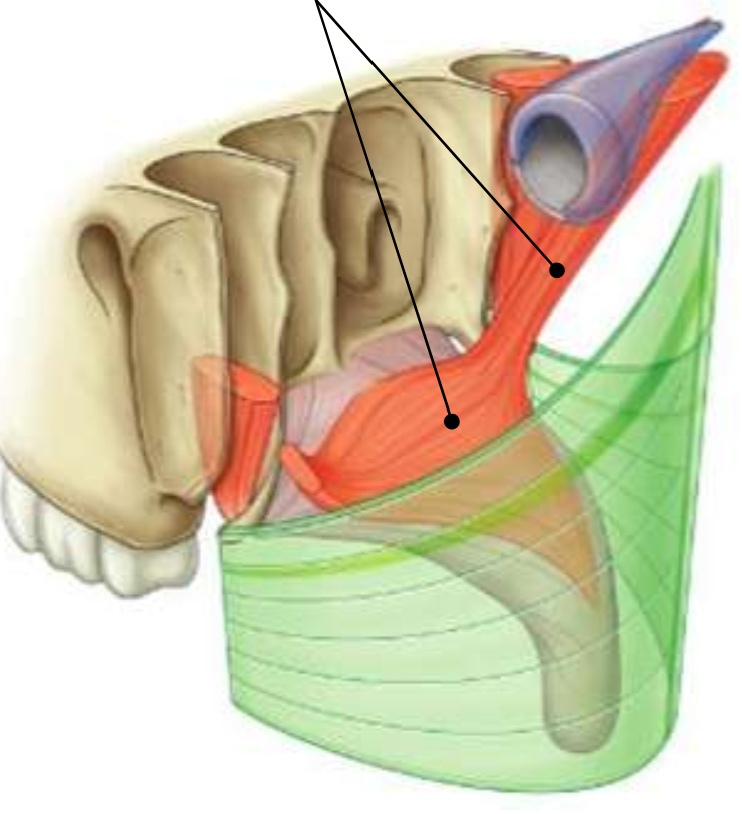

What muscle is this?

inferior constrictor

Which part of the muscle is 1?

thyropharyngeus

Which part of the muscle is 2?

cricopharyngeus

What are the attachments of this muscle?

oblique line of thyroid cartilage, cricothyroid tendon, cricoid cartilage → pharyngeal raphe

What is in the rectangle?

pharyngeal raphe

What is in the circle?

killians dehiscence